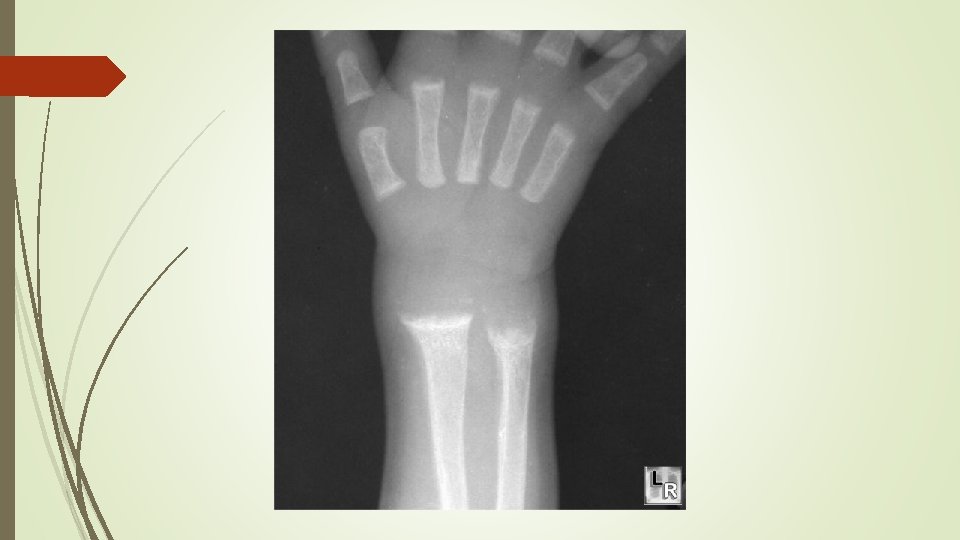

Radiographic findings Ø cupping Ø widening of the epiphyseal plate Ø fraying of the metaphysis

radiographs of a child with hypophosphatemic rickets, Metaphyseal widening in wrists And knees bone rarefaction

Radiographic Evaluation of Rickets Radiographs from 52 CRYSVITA-treated XLH patients in Study 1 and 13 patients in Study 2 were examined to assess XLH-related rickets using the 10 -point Thacher Rickets Severity Score (RSS) and the 7 -point Radiographic Global Impression of Change (RGI-C). The RSS score is assigned based on images of the wrist and knee from a single timepoint, with higher scores indicating greater rickets severity. The RGIC score is assigned based on side-by-side comparisons of wrist and knee radiographs from two timepoints, with higher scores indicating greater improvement in radiographic evidence of rickets. A RGI-C score of +2. 0 was defined as radiographic evidence of substantial healing. In Study 1, baseline mean (SD) RSS total score was 1. 9 (1. 17) in patients receiving CRYSVITA every two weeks. After 40 weeks of treatment with CRYSVITA, mean total RSS decreased from 1. 9 to 0. 8 (see Table 6). After 40 weeks of treatment with CRYSVITA, the mean RGI-C Global score was +1. 7 in patients receiving CRYSVITA every two weeks. Eighteen out of 26 patients achieved an RGI-C score of ≥ +2. 0. These findings were maintained at week 64 as shown in Table 6.